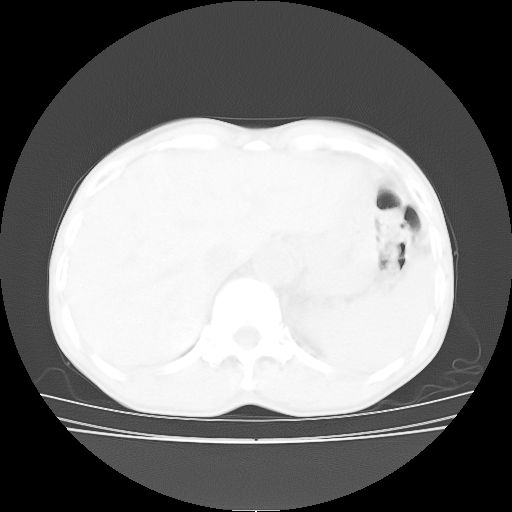

标题: CT25795:感冒后反复咳嗽两月余,痰中带血半月余。X诊断“肺 [打印本页]

标题: CT25795:感冒后反复咳嗽两月余,痰中带血半月余。X诊断“肺

1.双肺肺梗塞(理由:病灶呈三角形,与胸膜相连且局部胸膜肥厚,左心室增大)伴肺感染。

考虑两肺感染性病变,左肺上叶舌段肿瘤性病变待排;建议抗炎治疗后复查。